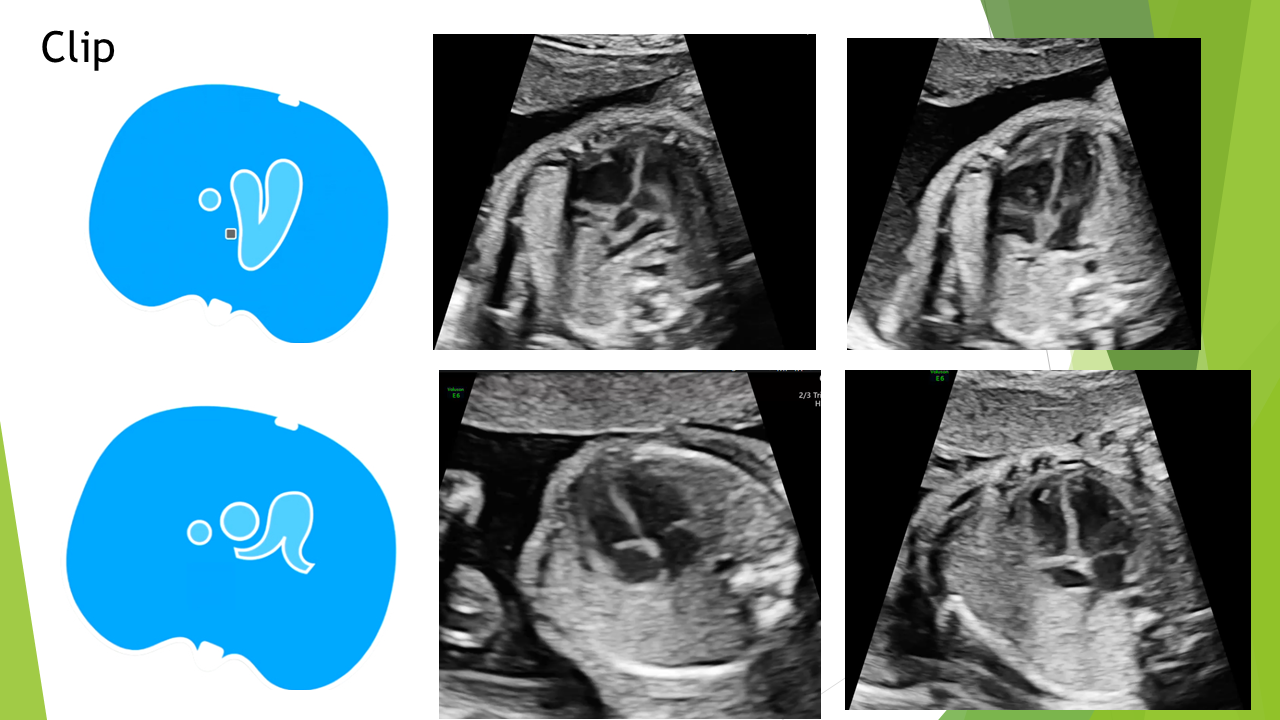

Siêu âm tim thai bằng phương pháp LEVY và STOS. 5-4-3-2-1